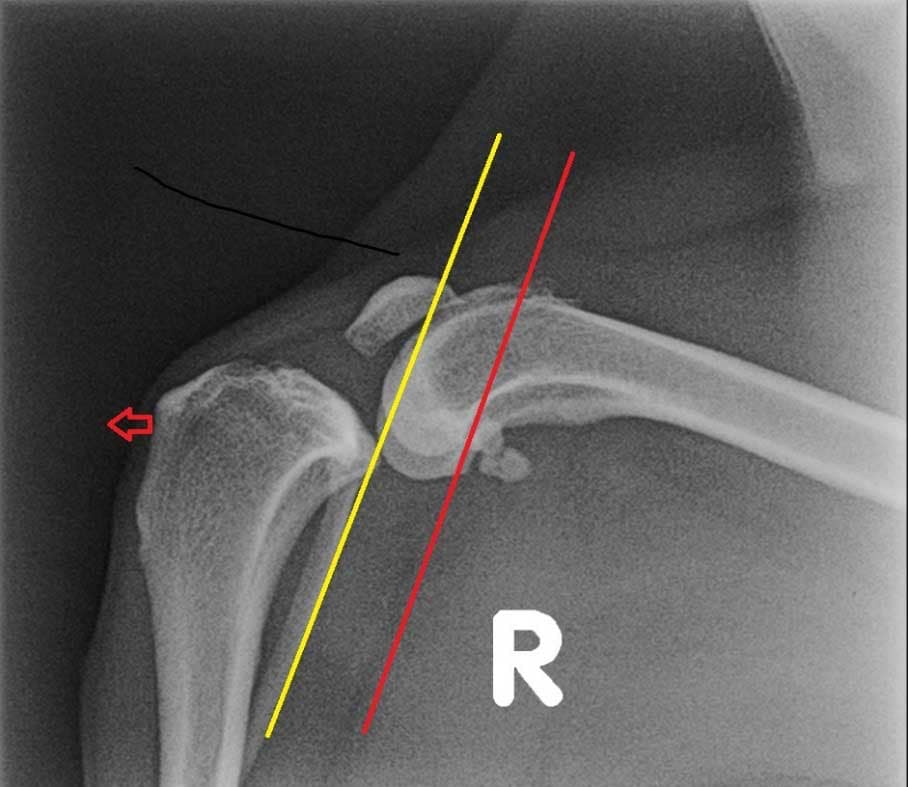

Hieronder links een foto van een gezonde knie en rechts een knie met gescheurde voorste kruisband. Hierbij valt op dat het onderbeen naar voren is geschoven bij de zieke knie.

TTA oftewel Tibial Tuberosity Advancement. De voorkant van het scheenbeen of tibia wordt hierbij ingezaagd en naar voren gebracht. Daardoor gaat ook de aanhechting van de kniepees naar voren.  Om deze verplaatsing te behouden wordt een TTA Rapid kooi geplaatst. Hierdoor veranderen de krachten die werken op het kniegewricht. Het onderbeen zal niet meer naar voren willen gaan, zodat de functie van een kruisband niet meer nodig is. Het goed bezenuwde en pijnlijke gewrichtskapsel staat niet meer op spanning. De knie komt als het ware in rust als de hond er op staat. Met als gevolg dat de knie rust krijgt om te herstellen. Ook komen er geen grote krachten meer op de meniscus in de knie. Eigenlijk maakt de chirurg van de hondenknie een mensenknie. Hiervoor moet er wel in het bot gezaagd en een implantaat met schroeven geplaatst worden. Dit maakt dat deze operatie duurder is dan een Flo techniek. Maar toch is de TTA Rapid goedkoper dan een oudere TTA of TPLO techniek. Hieronder een foto van een TTA Rapid kooi geplaatst in een nepknie.